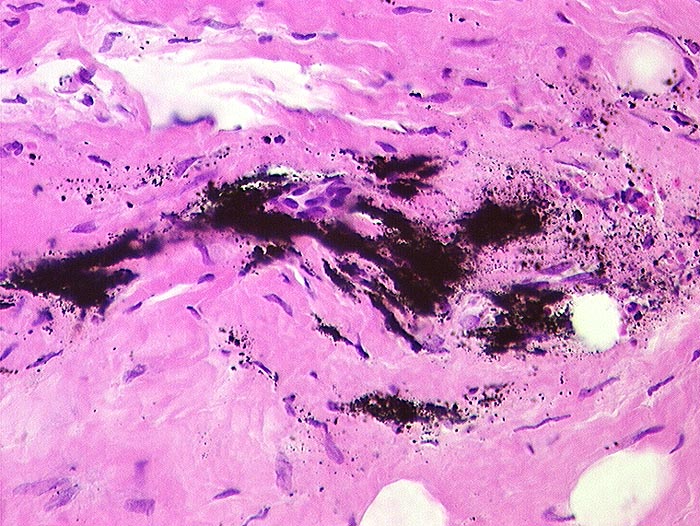

PathoPic ID 400 - Austausch Hüft-Totalprothese: Metallabrieb

Austausch Hüft-Totalprothese: Metallabrieb

Artefakt / Fremdkörper / Pigment

Gelenk, Hüfte

Weichteile

Metallabrieb: konfluierende feine schwarze Körnchen im Narbengewebe um das künstliche Hüftgelenk.

Histologie

59

männlich